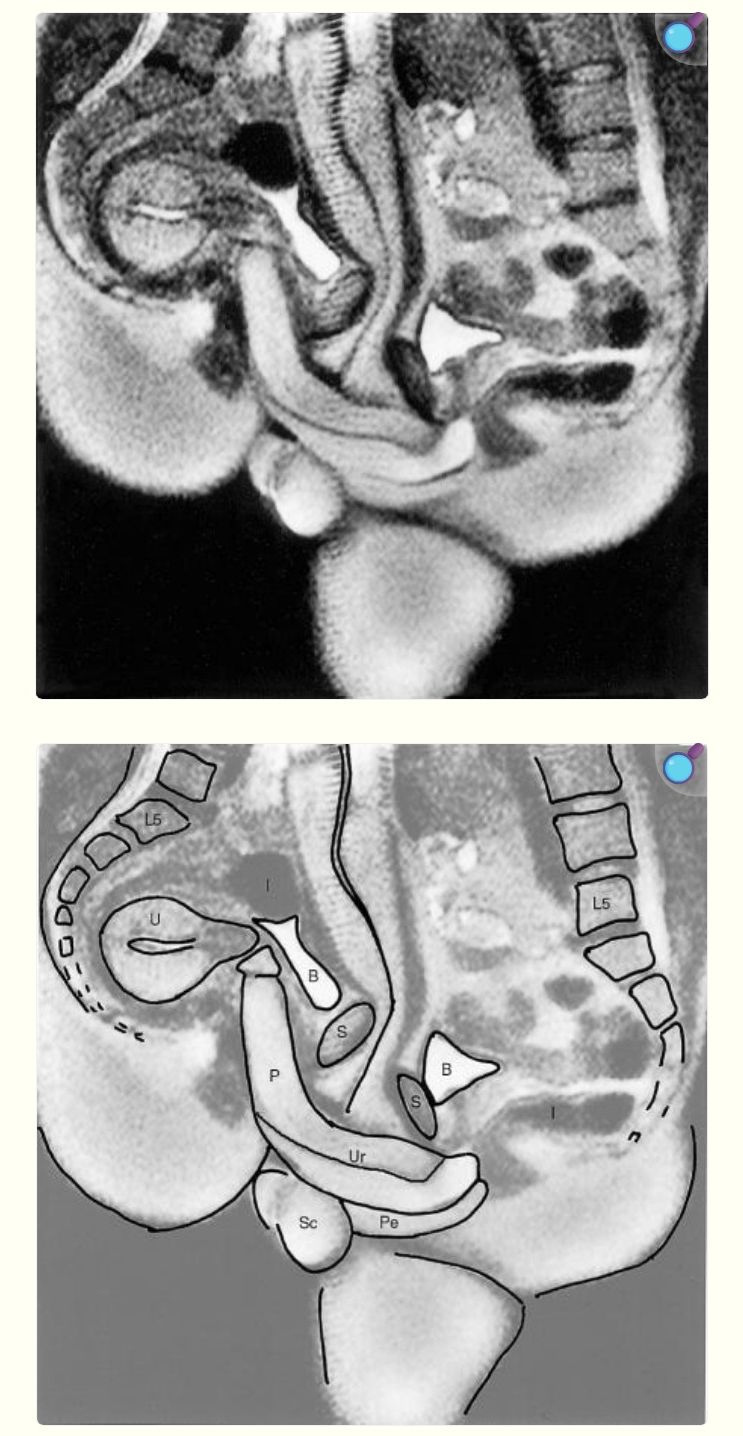

思ったより曲がっている…

性交中および女性の性的興奮時の男性および女性の性器のMRI

https://pmc.ncbi.nlm.nih.gov/articles/PMC28302/

P=penis Ur=urethra(尿道) Pe=perineum(会陰) U=uterus(子宮) S=symphysis(恥骨結合) B=bladder(膀胱) I=intestine(腸) L5=lumbar 5(腰椎) Sc=scrotum(陰嚢)

子宮コンコンが思ってた角度と違った

子宮の角度だいぶ個人差あるんだな

子宮って挿入後は普通にその位置になるんだ…

正常位でもちゃんと子宮が下側に来るんだな

Figure 2の形になるもんだと思ってた

正常位だから背中側に落ちるのかも